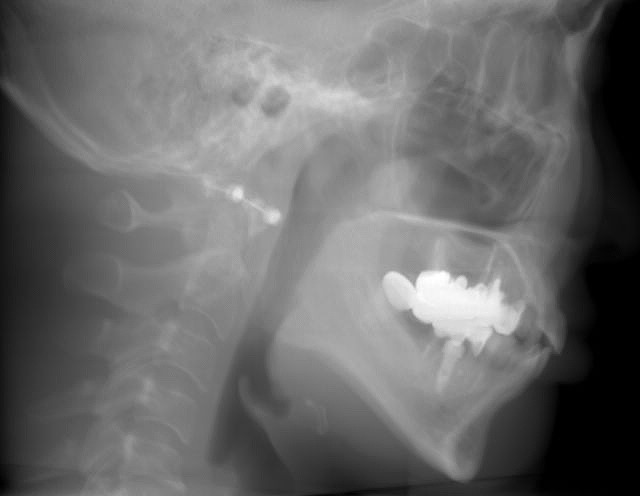

埋入前と後のセファロ像になります